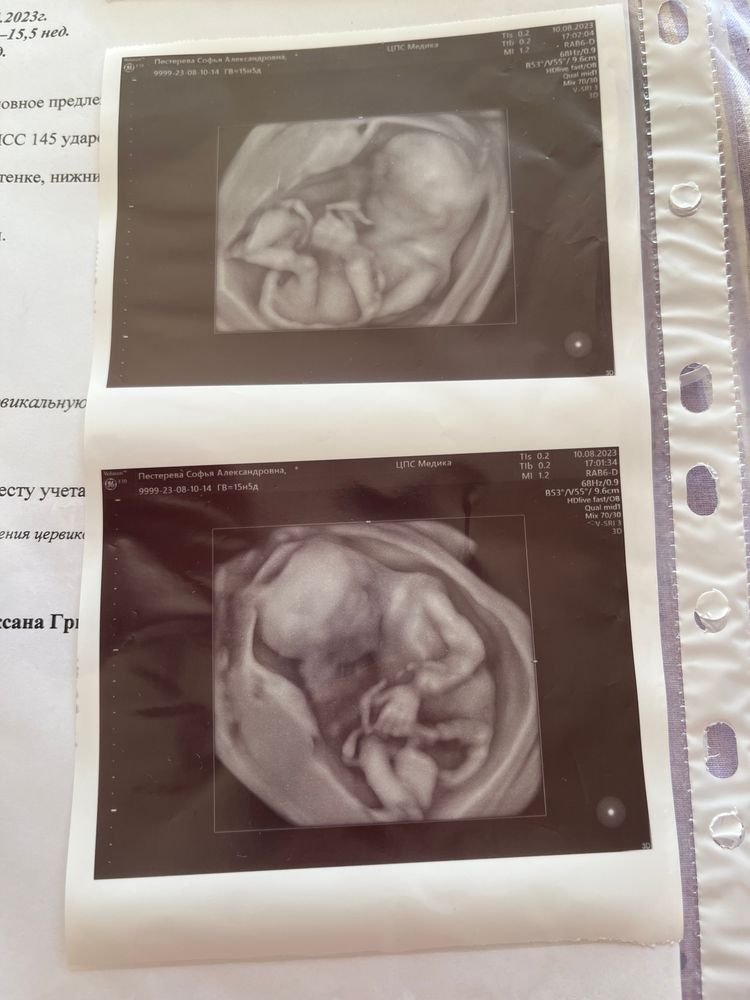

Товарищ помахал своей маленькой пятерней и засветил свои причиндалы, соответственно, на первом скрининге не ошиблись и мальчик это точно мальчик ☺️